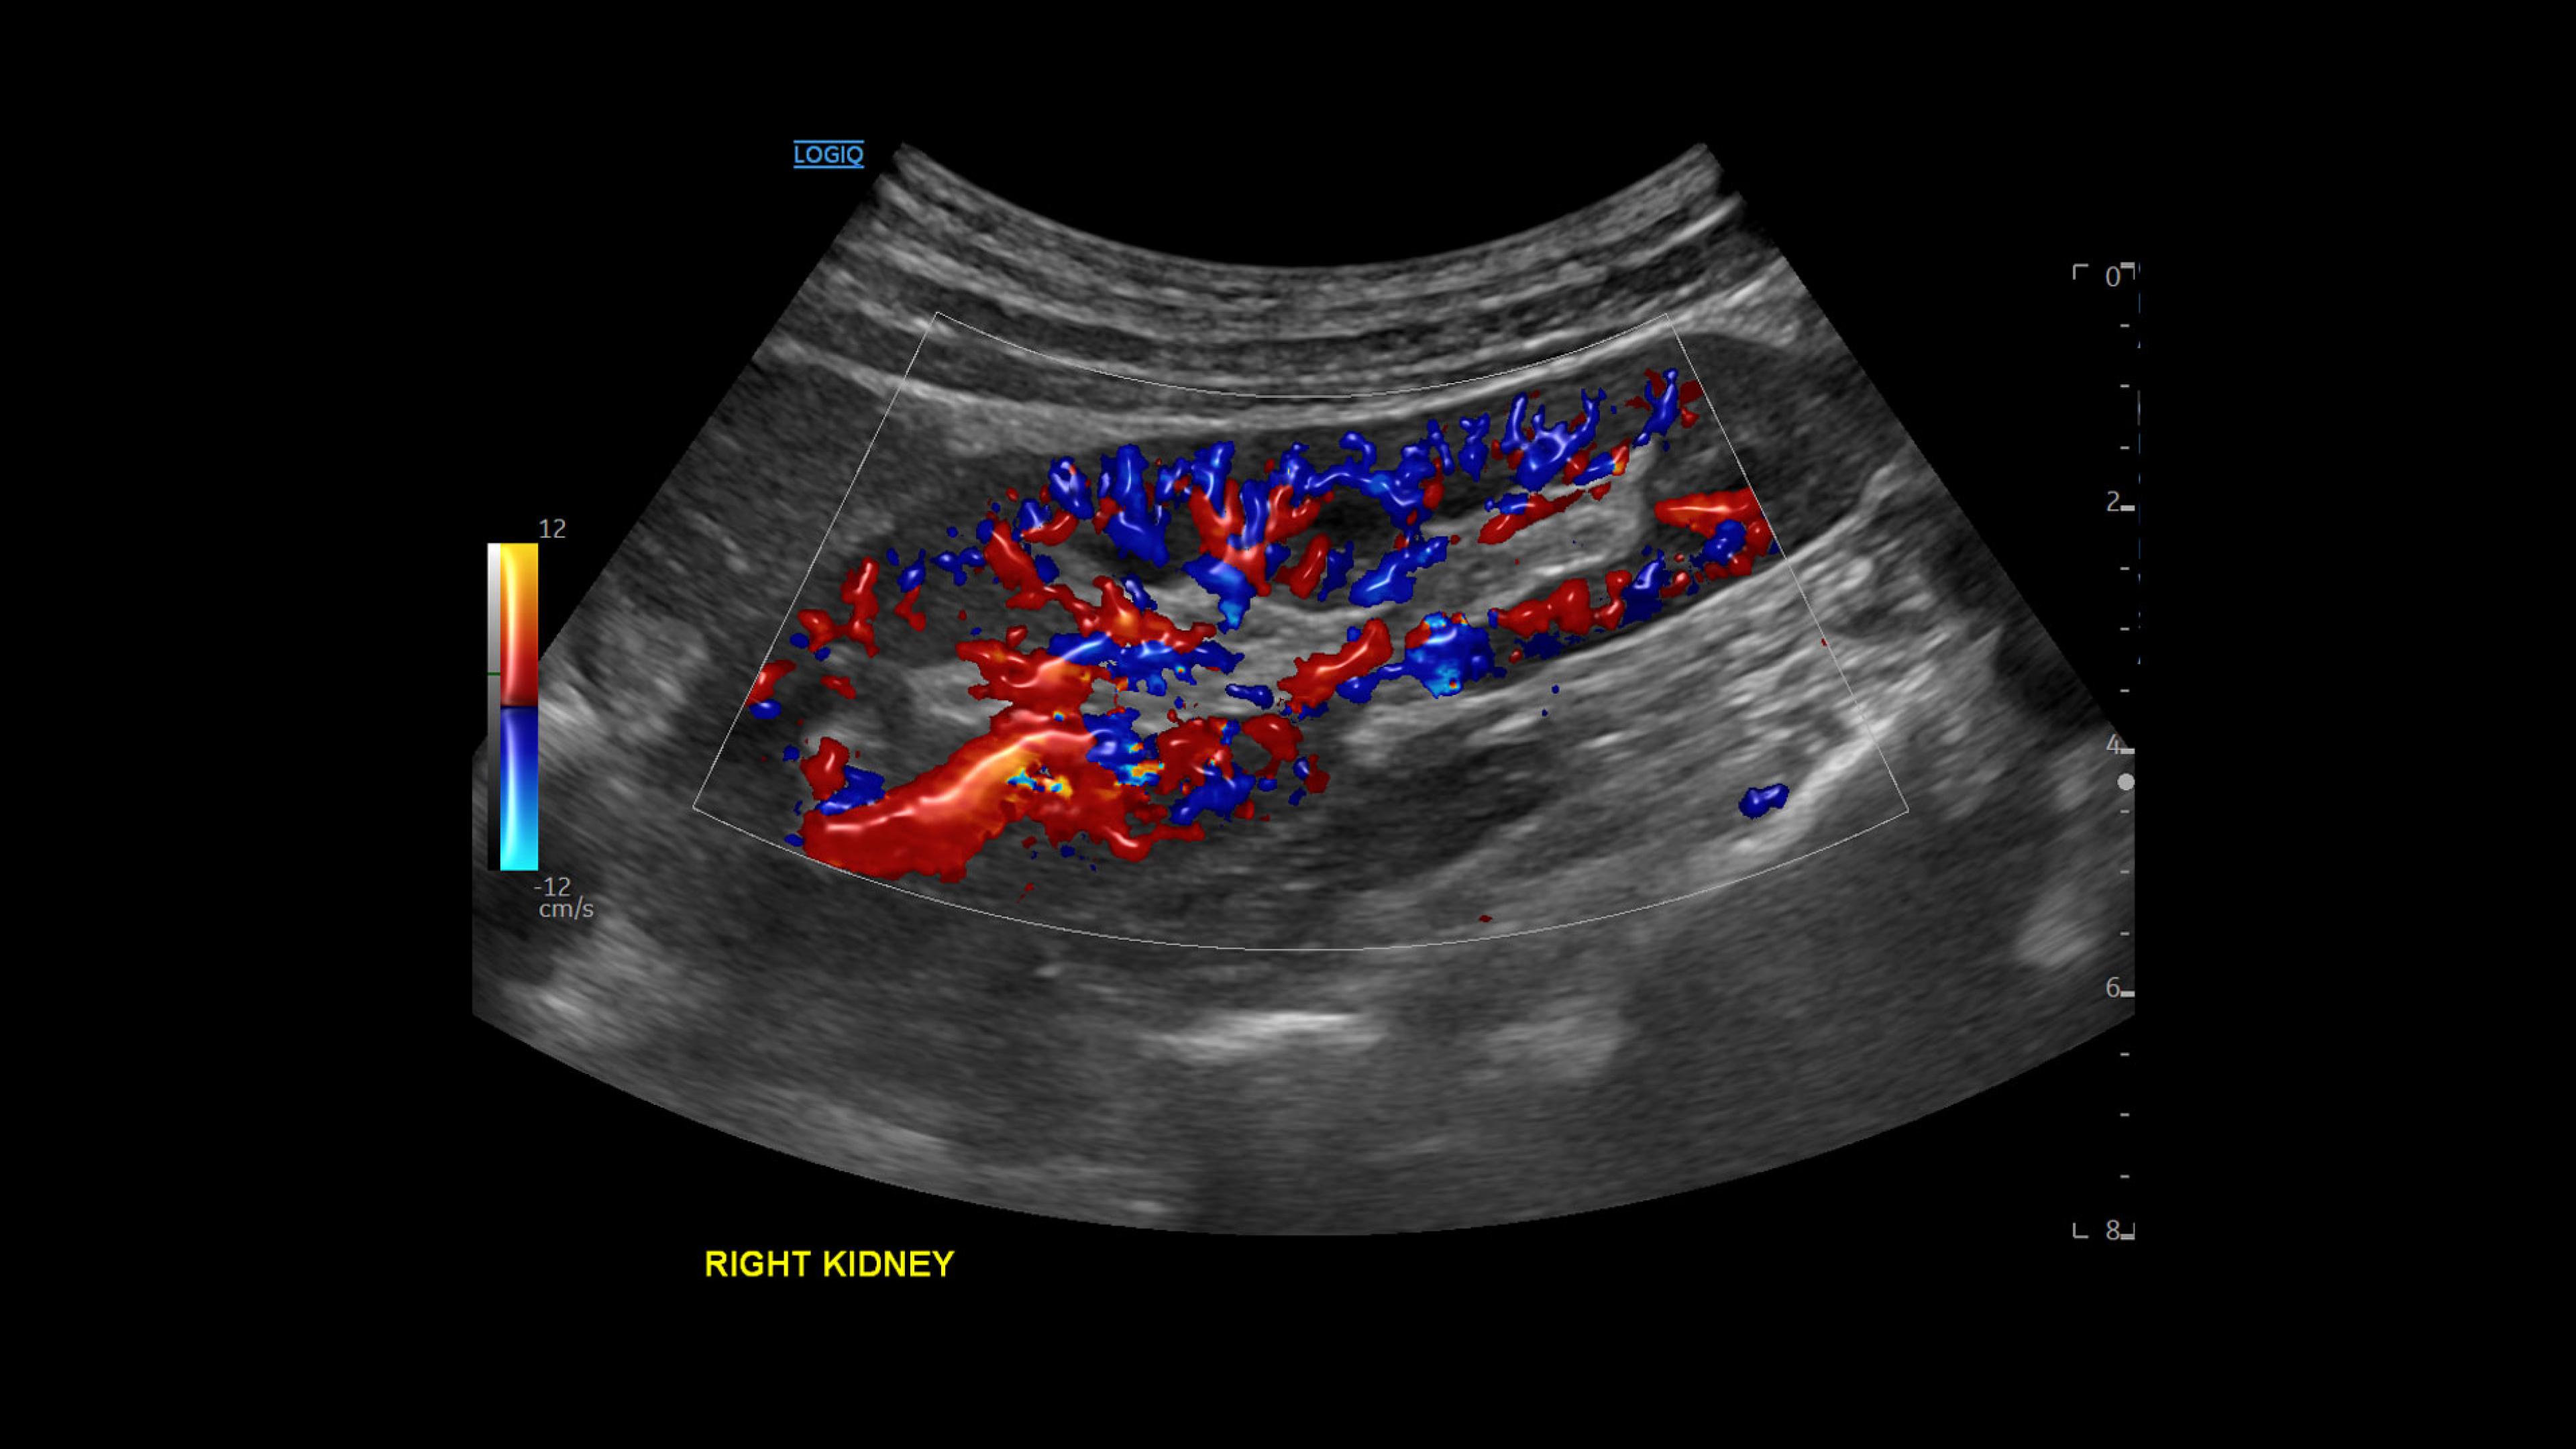

LOGIQ Totus™ Ultrasound

Multi-purpose excellence. Introducing LOGIQ Totus – a head-to-toe, comprehensive ultrasound experience that redefines your expectations.

The LOGIQ Totus™ system is a portable, multi‑purpose, comprehensive solution that combines AI‑powered workflow and decision‑support tools to enhance efficiency and versatility, while its high‑quality imaging supports head‑to‑toe diagnostic confidence.

• Rely on cSound™ Architecture, which delivers exceptional image quality and uniformity

• Leverage a wide range of transducers, including XDclear™, which produces high resolution images covering head-to-toe applications across clinical specialties or care areas